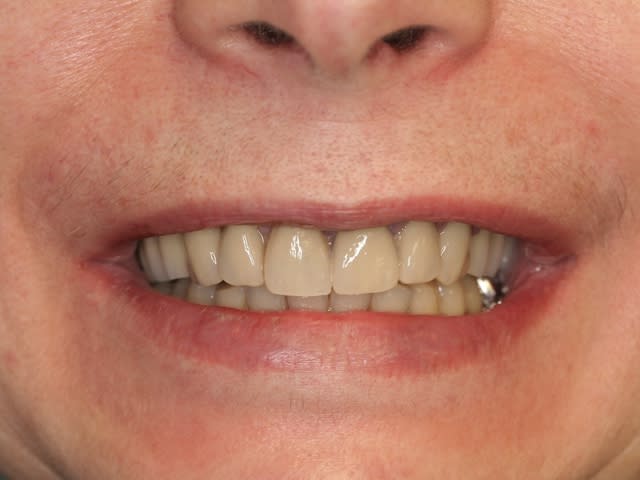

patiente jeune, femme, très joli sourire mais une couronne coulée sur 36...

Merci pour elle, elle approche les 60 ans.

Pluton a extrais (?) dents, posé (?) implants, a mise en charge immédiatement en 1 seul temps chirurgical un bride en (?), la patiente est revenue le lendemain pour lui faire un sourire.

juste avant de commencer une deuxième intervention sur une autre patiente, qui au passage va très bien aussi puisqu'elle était à sa boutique tout sourire aussi le lendemain...;-)